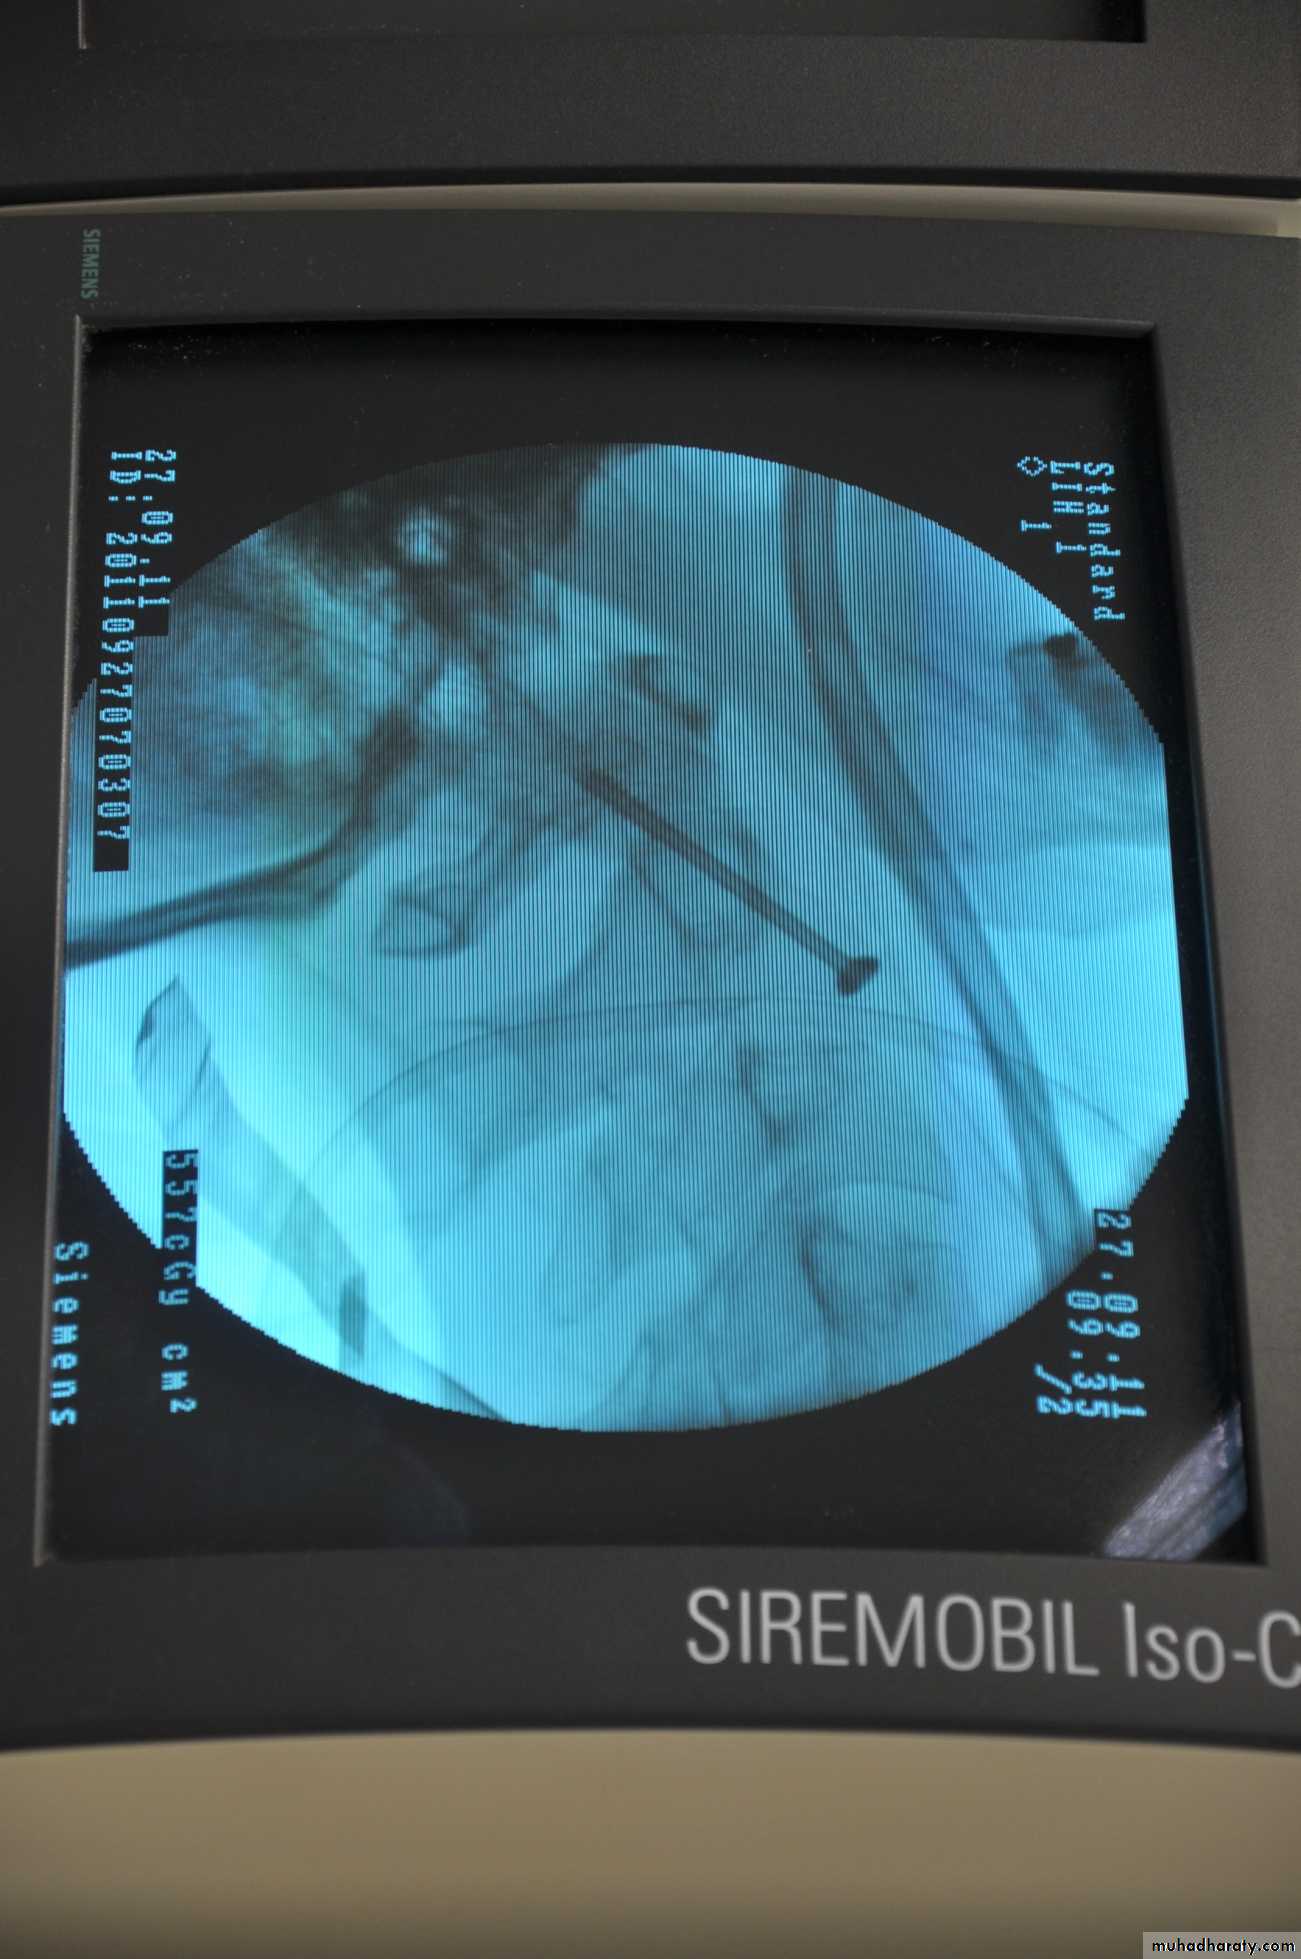

*Treatment :

Undisplaced # which is stable ,treated in a semi-rigid collar or halo-vest for12 weeks.Displaced # need either closed reduction with halo-vest or ,if this fail, open reduction &internal fixation.